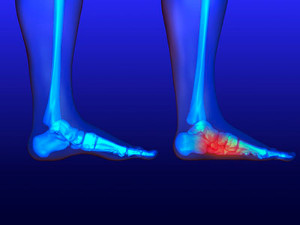

Gout, typically found in diabetic patients, is an unusually painful form of arthritis caused by elevated levels of uric acid in the bloodstream. The condition typically strikes the big joint on the big toe. It has also been known to strike the knees, elbows, fingers, ankles and wrists—generally anywhere that has a functioning, moving joint.

The high level of uric acid in a person’s bloodstream creates the condition known as hyperuricema—the main cause of gout. Genetic predisposition occurs in nine out of ten sufferers. The children of parents who suffer gout will have a two in ten chance of developing the condition as well.

This form of arthritis, being particularly painful, is the leftover uric acid crystallizing in the blood stream. The crystallized uric acid then travels to the space between joints where they rub, causing friction when the patient moves. Symptoms include: pain, redness, swelling, and inflammation. Additional side effects may include fatigue and fever, although reports of these effects are very rare. Some patients have reported that pain may intensify when the temperature drops, such as when you sleep.

Most cases of gout are easily diagnosed by a podiatrist’s assessment of the various symptoms. Defined tests can also be performed. A blood test to detect elevated levels of uric acid is often used as well as an x-ray to diagnose visible and chronic gout.